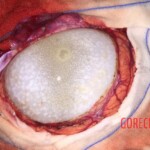

The cyst was said to have been growing for 8-10 years. It weighed a whopping 675 grams. If it had burst, the girl would have died instantly. But the cyst was successfully removed by surgery.

Nita’s parents admitted that they lived in a poor hygienic environment and did not even practice hygiene. The girl contracted the tapeworm that caused the cyst.